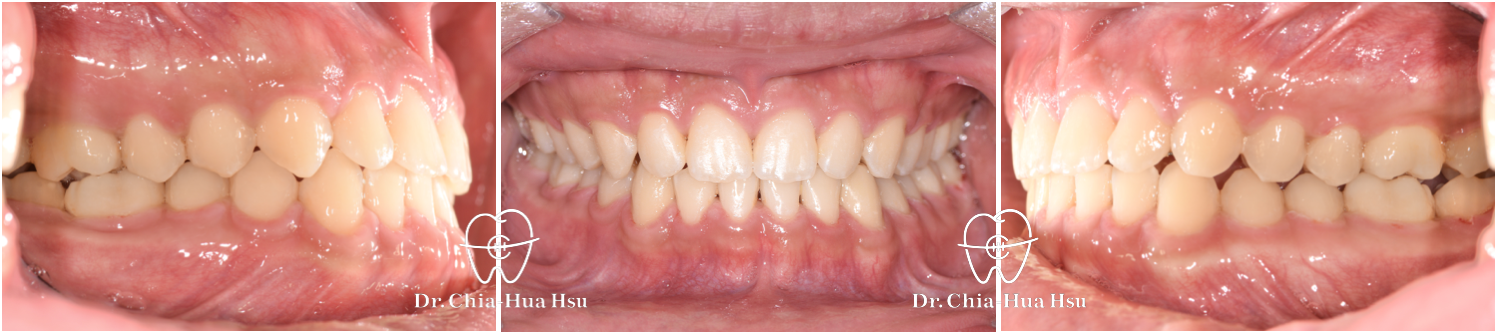

咬合不正、錯咬、咬合平面傾斜

青少年矯正 | 金屬矯正 | 上顎擴弓 | 非拔牙治療

治療前

治療後